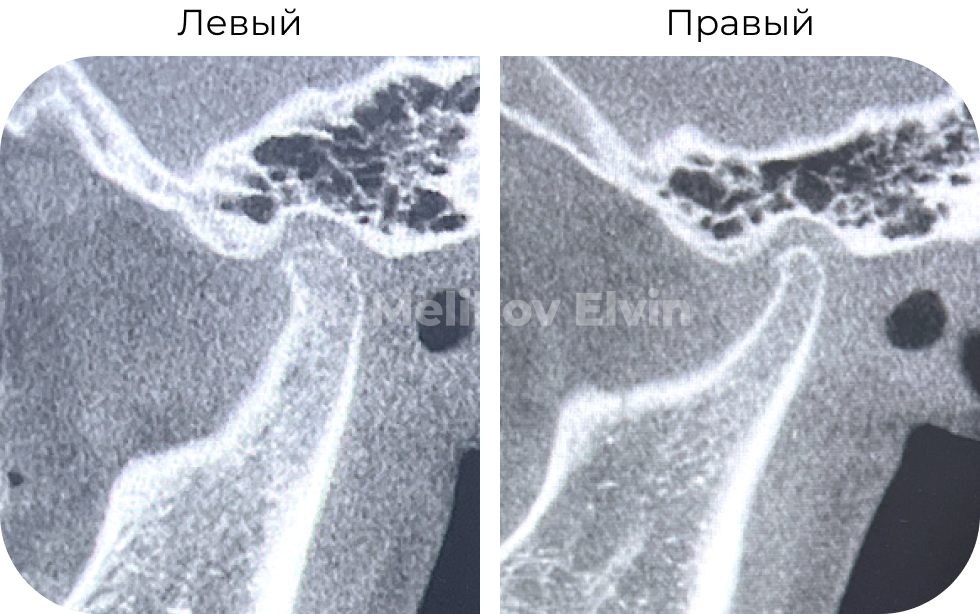

КТ после лечения